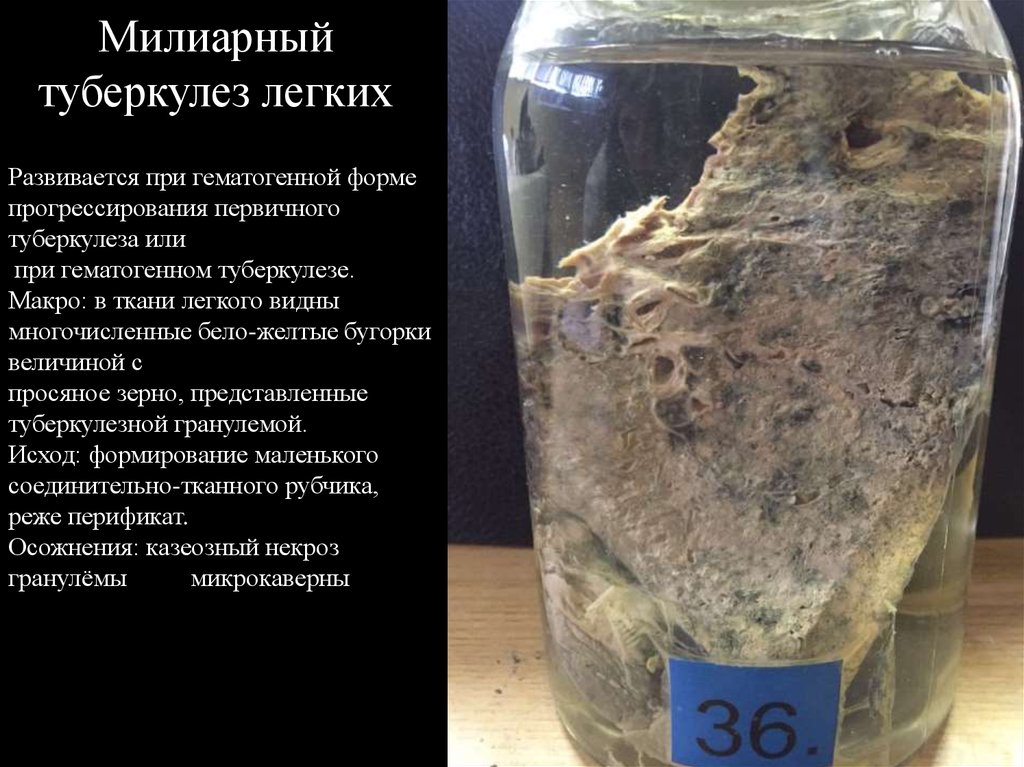

Микроскопический взгляд на мишитарный туберкулез легкого: фотодокументация